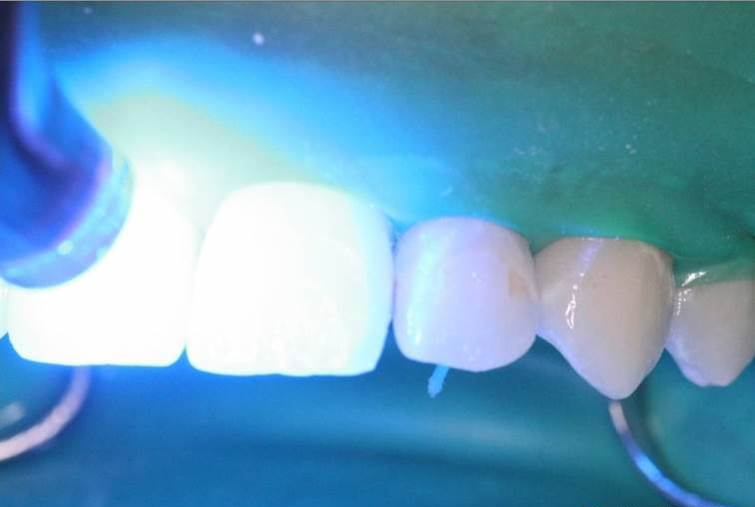

8、去除多余材料后,每个牙面光照40秒